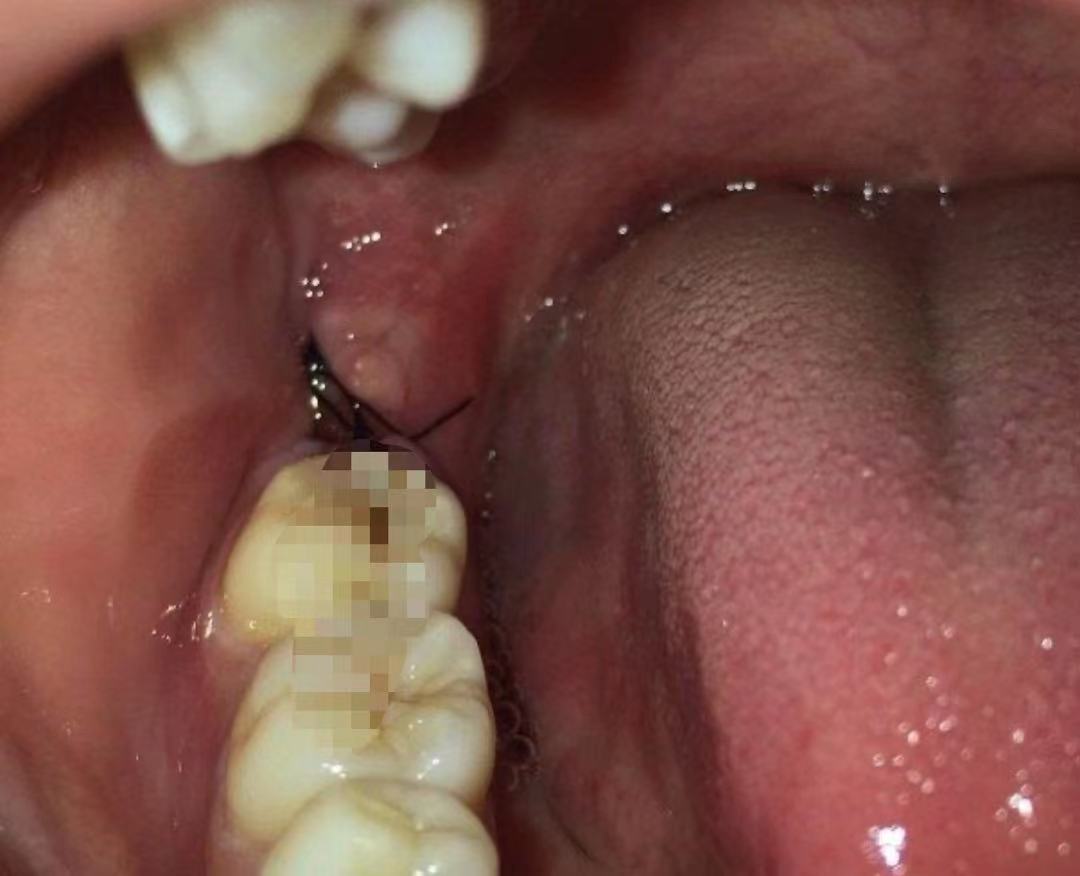

(6)最后缝合止血。